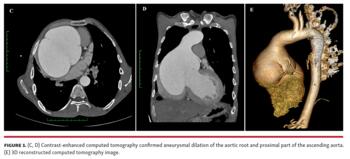

A 25-year-old man came to our clinic with complaints of exertional palpitations and dyspnea. He had skeletal features suggestive of Marfan’s syndrome, including increased arm span, wrist and thumb signs, kyphoscoliosis, and pectus carinatum. Examination revealed a wide pulse pressure, cardiomegaly, and early diastolic murmur of aortic regurgitation. The echocardiogram was peculiar in showing a massively dilated aortic root, apparently compressing the surrounding cardiac structures (Figures 1A and 1B, Video 1). There was severe aortic regurgitation with a dilated and dysfunctional left ventricle. Contrast-enhanced computed tomography (Figures 1C and 1D) confirmed aneurysmal dilation of the aortic root and the proximal part of the ascending aorta. The largest transverse diameter of the aorta was 14.2 cm at the level of the sinuses of Valsalva. No dissection flap or intramural hematoma was observed. The patient was advised to undergo Bentall procedure for replacement of the aortic valve, aortic root, and ascending aorta. He was, however, lost to follow-up.